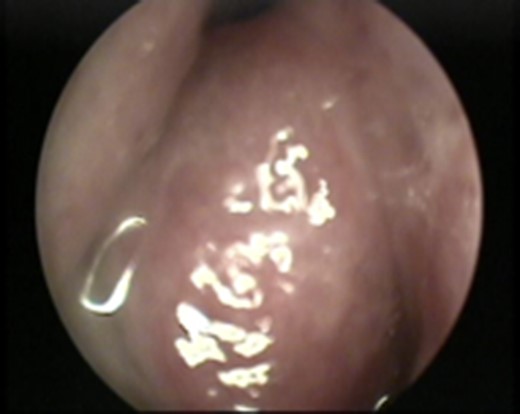

A 24-year-old male patient who presented with a history of right nasal obstruction, right eye pain, lower eyelid swelling and orbital swelling. Endoscopic examination revealed an obstructive mass occupying the right nasal cavity (Fig. 1). Cranial nerves were intact. The result of hematological and biochemical investigations were within normal limits.

Nasal endoscopy image showing a soft tissue mass arising from the right lateral nasal wall.